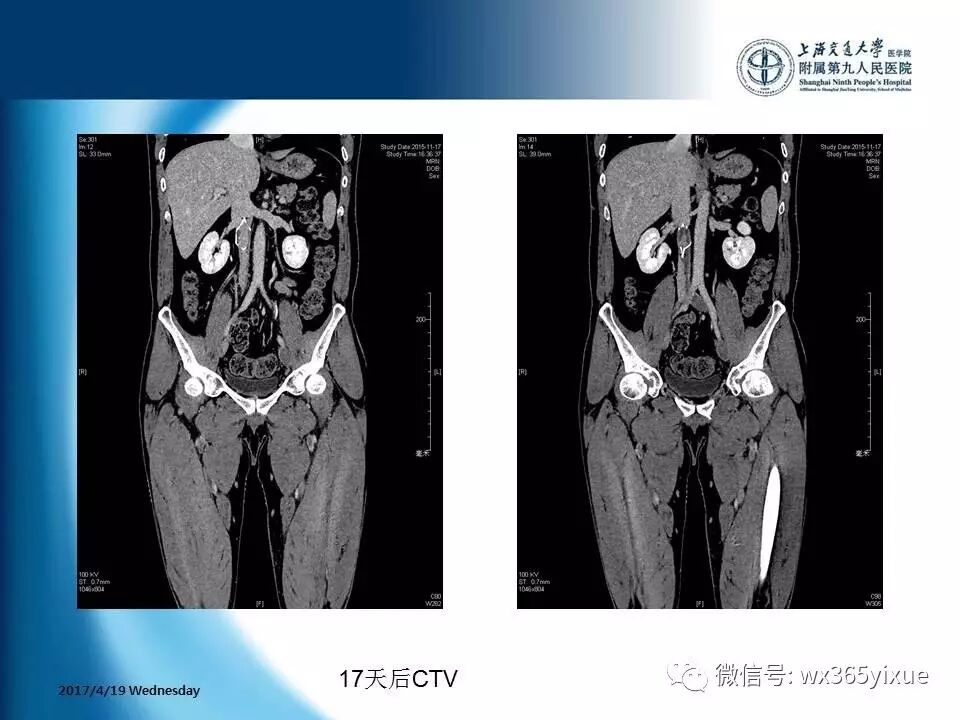

【热点课件】陆信武:滤器相关下腔静脉血栓成的腔内治疗

上海交通大学医学院附属第九人民医院